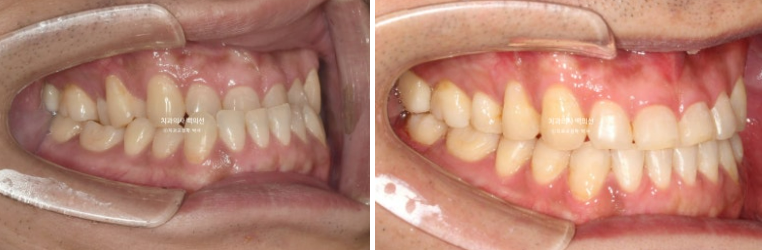

어금니 교합은 좋습니다.

23.07~25.04

앞니 거꾸로 물리는 반대교합은 해소가 되었고

안모의 변화가 눈에 띕니다.

교정만으로 아래턱이 뒤로 들어가진 않지만 앞니 반대교합이 해결이 되면 아래 앞니가 뒤로 들어가면서 아랫입술이 뒤로 들어갑니다.

이로써 경우에 따라서 턱이 더 도드라져 보이는 경우도 있지만 입술 밸런스가 좋아지면서 오히려 주걱턱이 완화되어 보이는 경우도 있습니다.